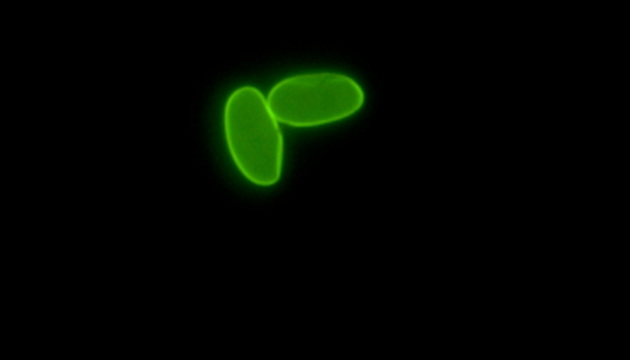

兩蟲指的是賈第鞭毛蟲(Giardia)和隱孢子蟲(Cryptosporidium),它們是主要的水源性原生動物寄生蟲,通過被污染的飲用水或食物感染人類,引起腹瀉等疾病,且大多數(shù)抗生素對其無效,嚴(yán)重威脅水質(zhì)安全和人類健康。

顯微成像在檢測兩蟲中扮演關(guān)鍵角色,通過免疫熒光法結(jié)合專業(yè)的熒光顯微鏡,能高效區(qū)分并識別水體中的賈第鞭毛蟲和隱孢子蟲,確保飲用水安全。這種方法提高了檢測的準(zhǔn)確性和效率。